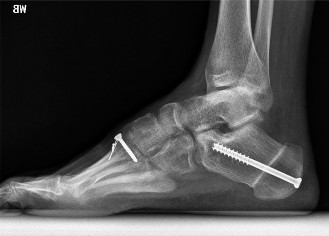

The correct answer is (B). Correction of the hindfoot varus with Coleman block testing confirms that the subtalar joint remains flexible and that the cavus deformity is driving the hindfoot varus. A dorsiflexion osteotomy of the first ray will raise the first metatarsal from its pathologic plantar-flexed position. With subsequent weight bearing, the head of the first metatarsal must still contact the ground. When doing so postoperatively, however, it forces the hindfoot out of pathologic varus into a more neutral position. This can be supplemented with a calcaneal osteotomy with lateral

heel slide if necessary (Fig. 5–6); a medial slide would accentuate the hindfoot varus deformity.

#### Figure 5–6 Dorsiflexion osteotomy of the first ray and calcaneal osteotomy with lateral heel slide for pes cavus. Objectives: Did you learn...?